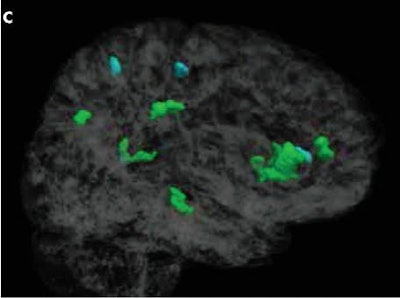

Based on fractional anisotropy results from DTI-MR images, the researchers observed three brain regions in male athletes where more headings were significantly associated with lower fractional anisotropy. Only in the left temporal white matter was more heading associated with significantly higher fractional anisotropy (p < 0.01 across more than 100 contiguous voxels).

For the female athletes, greater heading exposure was significantly associated with lower fractional anisotropy in eight brain regions. Increased fractional anisotropy was evident only in the left frontal white matter (p < 0.01 across more than 100 contiguous voxels). In seven of the eight brain regions, the association between heading and fractional anisotropy was stronger in women than in men.

Most important, changes in fractional anisotropy were detected across 2,121 mm3 of white matter in women, compared with 408 mm3 of white matter in men.